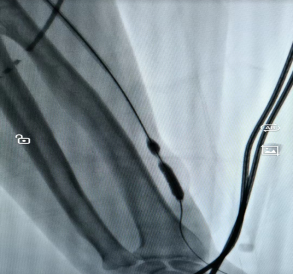

对于长期做透析的朋友来说,血管通路就是“生命线”,这条“路”一旦堵了(比如狭窄、长血栓),透析效果会变差,严重的还可能危及生命。以前遇到这种情况,不少人担心要“开大刀”,现在有了更简单的办法。 贵州航天医院肾脏风湿科开展了一项微创技术——血管通路介入治疗(用一根细针、一根微导管,顺着血管把堵塞的地方“疏通”开),不用大切口,也能解决内瘘狭窄、血栓、闭塞这些麻烦事。 这项技术是怎么做的? 医生在影像设备(彩超、DSA)的实时引导下,从皮肤上扎一个小针眼,把导管送到血管病变的位置,然后用球囊撑开狭窄的地方、或者溶掉血栓、必要时放个小支架,整个过程创伤小、恢复快、还能反复做。 主要能解决哪些问题? ※动静脉内瘘狭窄或闭塞:做球囊扩张术(PTA),是目前首选的办法。 ※内瘘里长了血栓同时伴有狭窄:溶栓+球囊扩张。 ※中心静脉(比如胸口附近的血管)狭窄或闭塞:球囊扩张或放支架。 ※需要放透析长期导管但位置不好放:精准置管。 哪些人适合做? 1.透析时血流量不够、静脉压力高、穿刺越来越困难。 2.彩超检查发现内瘘狭窄超过50%,或者内瘘发育不好、术后又窄了。 3.内瘘完全堵死,想尽量保住原来的血管。 4.手臂或脸肿了,可能是中心静脉堵了。 5.自身血管条件差,反复置管失败,或者身体受不了开刀手术。 6.目前脖子上或大腿上带着长期透析管,想拔掉管子改用自己的内瘘。 这项技术好在哪? ☑微创损伤小:就一个小针眼,几乎不留疤,局部麻醉就行,对身体影响小。 ☑看得清,打得准:彩超或DSA实时引导,医生能清楚看到血管,避开重要部位。 ☑恢复快:多数患者做完手术当天就能下床活动,内瘘很快就能再用上,不用等。 ☑省着用血管:球囊扩张可以反复做,尽量保住自己的血管。 ☑能重复治疗:以后万一再堵了,还可以再做介入,不用“一刀切”重新建一条通路。 ☑减少感染风险:成功救回内瘘后,很多患者可以拔掉临时或长期的透析导管,感染风险更低,也保护了中心静脉。 透析小常识: 1.透析就是帮助受损的肾脏“洗血”,清除体内多余水分和代谢废物,多数人每周做2-3次,每次约4小时。 2.内瘘是透析患者手臂上通过手术将动脉和静脉连接起来的一种血管通路,摸上去会有“嗡嗡”的震颤感,是透析治疗的关键通道,平时要护好内瘘——每天用手摸一摸震颤是否正常,别压着内瘘侧手臂睡觉,不提重物,不在这侧抽血或量血压。 3.饮食上注意少喝水(两次透析间体重增长不超过干体重的3%-5%),少吃盐和含磷高的食物(如坚果、动物内脏、可乐),适当吃鸡蛋、瘦肉、鱼肉等优质蛋白。 4.如果发现内瘘震颤变弱或消失、手臂肿胀、透析时血流量不足,立即告诉医生。 注:部分图片来源于网络,如有侵权,请联系删除。 贵州航天医院 肾脏风湿科专家简介 冯远军 肾脏风湿、肝胆外科党支部书记,肾脏风湿科主任,主任医师 临床擅长:对慢性肾脏病、急性肾损伤、急慢性肾小球肾炎、肾病综合症、风湿性疾病、间质性肾炎、肾小管损伤等疾病的诊治及血液透析技术、动静脉内瘘成形术及疑难病例的诊治具有丰富的临床经验。 曾在上海市第一人民医院及贵阳市第一人民医院进修学习,贵州省医学会肾脏病学分会第五届委员会委员,遵义市医学会肾脏病学分会第一届委员会副主任委员,遵义市医学会风湿病学分会第一届委员会副主任委员,荣获“贵州航天劳动模范、遵义市汇川区先进工作者”,遵义市医疗事故鉴定专家库成员,主持省市级科研项目4项,完成4项,近5年发表论文10余篇,北大核心期刊1篇。 王卫华 肾脏风湿科主任医师 临床擅长:从事临床工作28年,擅长尿毒症患者血管通路的建设及维护(如标准和高位动静脉内瘘术、取栓+内瘘重建术、内瘘狭窄球囊扩张术、长期中心静脉置管术及肾穿刺活检术)等手术,对原发性和继发性肾病综合征、急、慢性肾小球肾炎、慢性肾脏病、泌尿系感染、结缔组织病、急性中毒、痛风、贫血、血小板减少症等疾病诊治及血液透析技术应用等具有丰富的临床经验。 1995年毕业于遵义医学院临床医学系,曾前往重庆医科大学进修学习肾脏疾病及血液净化,遵义市医学会肾脏病学分会常务委员,遵义市血液净化质量控制中心委员,先后发表肾病专业省部级医学刊物医学论文8篇,主持市级科研项目2项。 李丽华 中共党员,肾脏风湿科副主任医师 临床擅长:从事临床工作17年,对慢性肾脏病、急性肾损伤、急慢性肾小球肾炎、肾病综合征、风湿性疾病、间质性肾炎、肾小管损伤、急慢性肾衰竭的血液透析、CRRT治疗以及血管通路的建设维护等具有丰富的临床诊疗经验。 2006年毕业于遵义医学院临床专业,曾在遵义医学院附属医院完成住院医生规范化培养,并前往第三军医大学新桥医院、珠海市人民医院进修学习,中华医学会遵义市肾脏病学分会委员,遵义中医药学会肾病专业委员会委员,遵义市血液净化质量控制中心委员,遵义市医学会血液学分会委员会委员,发表省部级医学刊物医学论文4篇,主持参与省级科研课题1项,主持参与市级科研课题1项,院级新技术6项,获得本专业授权实用新型专利3项。 李 玫 中共党员,肾脏风湿科副主任医师 临床擅长:从事临床工作15年,对慢性肾脏病、急性肾损伤、急慢性肾小球肾炎、肾病综合征、风湿性疾病、间质性肾炎、肾小管损伤等疾病的诊治具有丰富的临床经验,擅长血液透析技术、动静脉内瘘成形术等。 2008年毕业于遵义医学院临床医学系,曾前往遵义医学院附属医院进修学习肾脏病与血液净化相关技术,遵义市医学会肾脏病学分会委员,发表肾病专业省部级医学刊物医学论文4篇。 贵州航天医院肾脏风湿科简介 • ✦ 基本情况 ✦ • 贵州航天医院肾脏风湿科2017年建立,住院患者承载能力达到50人左右,透析治疗服务惠及280余人的患者群体,在学科建设、高端医疗设备引进及专业技术队伍已达到区域内领先水平。科室共有医护人员46名,副高级以上专家7名,亚专业设置齐全,涵盖肾脏疾病、风湿免疫疾病药物治疗、透析治疗及透析通路维护等多个专业领域,为患者提供全面的诊疗服务。配备了尖端的医疗设备与智能化的辅助系统,包括透析机、CRRT机等设备。 • ✦ 专科特色 ✦ • (一)肾脏病治疗领域:专精于血液透析、血液透析滤过、血液灌流、血浆置换、CRRT等尖端技术,致力于为患者量身打造个性化的肾脏替代治疗方案。 (二)在风湿病治疗方面:凭借生物制剂、免疫抑制剂等前沿药物,结合患者的具体情况,精心策划个体化的治疗策略,有效减轻患者症状,显著提升生活质量。 (三)超声引导下球囊扩张术:内瘘狭窄是内瘘最常见的并发症之一,我们采用超声引导下球囊扩张术,通过微创方式恢复内瘘通畅,有效避免了传统手术带来的创伤和痛苦。 (四)内瘘血栓溶栓治疗、取栓术:血栓形成是内瘘功能丧失的主要原因之一,根据患者具体情况,采用溶栓治疗、取栓术等多种手段,确保患者及时恢复透析治疗。 (五)内瘘动脉瘤形成治疗:动脉瘤是由于内瘘局部血流动力学改变引起的血管扩张性疾病,采取佩戴弹力绷带、手术修复等措施,防止动脉瘤进一步发展和破裂。 (六)内瘘感染治疗:内瘘感染是内瘘并发症中最为严重的类型之一,一般采用敏感抗生素进行抗感染治疗,严重者采取手术清创等措施。 (七)内瘘窃血综合征治疗:是由于内瘘建立后,远端肢体血流减少引起的一系列症状,通过调整透析方案、改善内瘘血流分布及必要时重建内瘘等措施,有效缓解患者的症状并提高其生活质量。 • ✦ 诊疗范围 ✦ • 擅长治疗急慢性肾炎、肾病综合征、肾衰竭等肾脏疾病;擅长治疗类风湿关节炎、系统性红斑狼疮、干燥综合征等风湿免疫性疾病,并为患者提供健康教育与康复指导,帮助患者更好地管理疾病,提高生活质量。 end